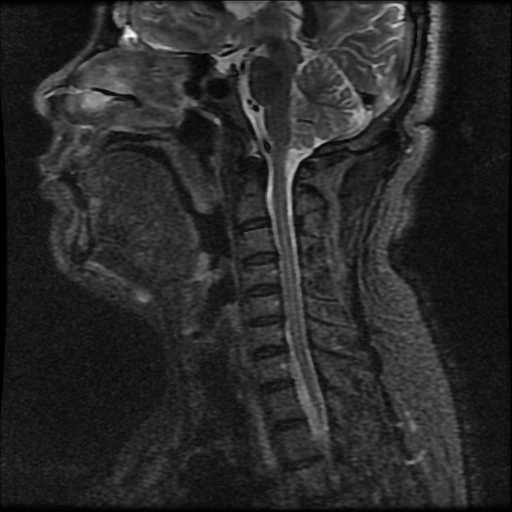

近日,一位50岁男性患者3个月前无明显诱因出现颈部及左上肢疼痛不适,症状进行性加重,休息后无明显缓解,疼痛难忍,严重影响正常生活,故到当地医院就诊,治疗上给予营养神经、止痛、中医理疗等(具体不详),效果一直欠佳,当地医院给予行颈椎MRI检查等显示:颈椎间盘膨出(下图核磁),患者就诊多家医院均认为无法明确疼痛原因,没有具体的治疗方案,后患者转至新疆自治区人民医院就诊。

患者入住新疆自治区医院脊柱一科后,虽然查体为神经根型颈椎病的体征,但核磁显示仅仅是颈椎间盘的膨出,无法解释患者左上肢抽痛不适的原因,我院驻疆专家在仔细查看患者的各项影像学检查后发现,在患者颈椎斜位片可见钩椎关节明显增生,椎间孔狭窄,虽然无法显示神经根,但凭借丰富的临床经验,杨宝辉副主任医师考虑患者左上肢抽痛原因即在于增生的钩椎关节对神经根的压迫,遂决定给予行颈椎钩椎关节切除术。